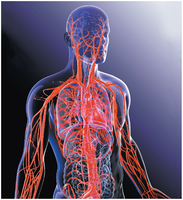

The cardiovascular system is composed of a complex network of blood vessels that transport blood throughout the body. There are two main circuits:

Pulmonary circuit: Carries blood to and from the lungs for gas exchange.

Systemic circuit: Delivers blood to the rest of the body and returns it to the heart.

Both circuits operate simultaneously with each heartbeat, ensuring efficient oxygen and nutrient delivery and waste removal.